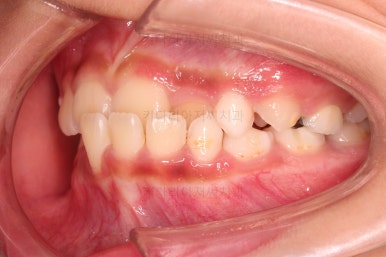

1. 초진

초진 시 입안의 모습입니다.

가장 눈에 띄는 건, 아랫니가 윗니보다 앞에 나와있는 부정교합인데요.